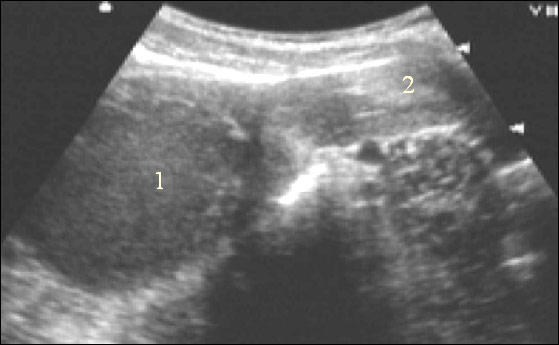

Гематометра (УЗИ-исследование)